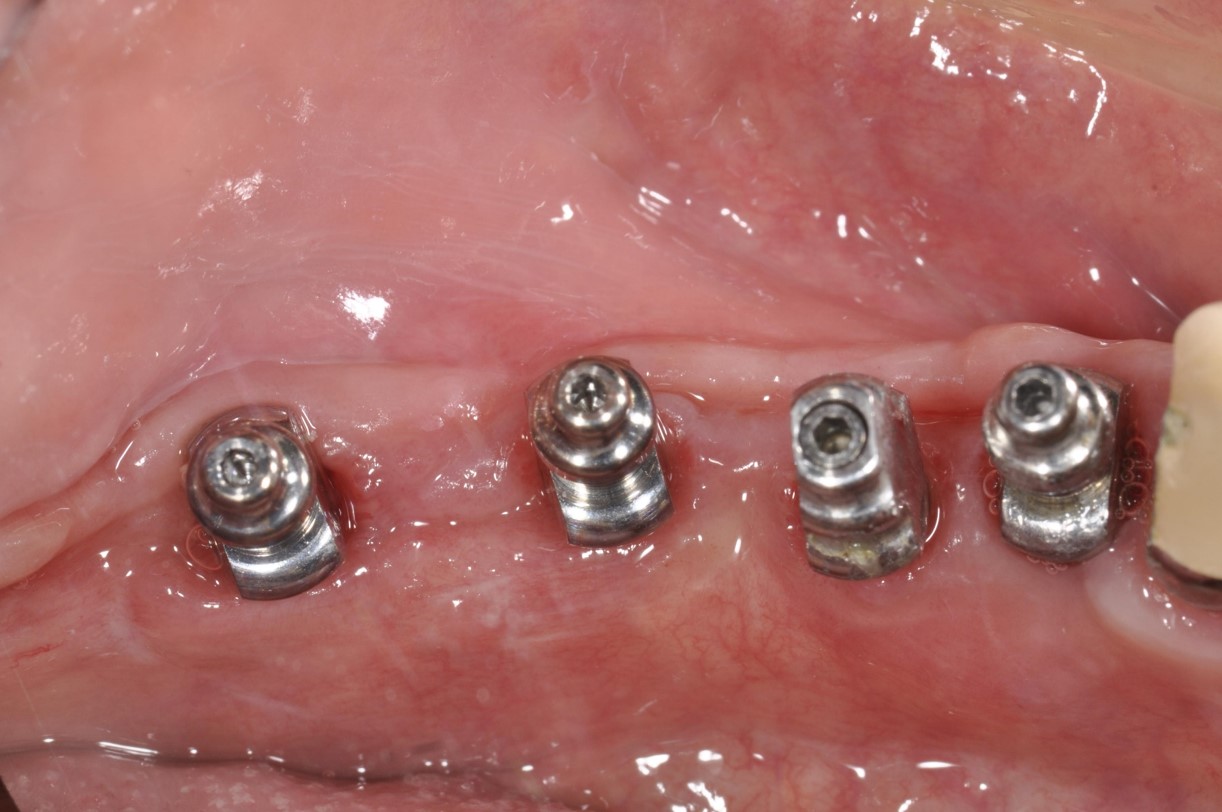

▼植牙1個月後追蹤

植牙1個月後追蹤

植體印模:#34-37